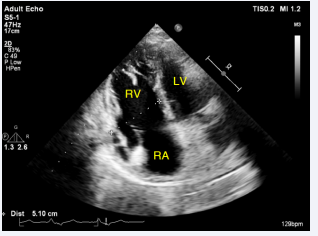

A 25-year-old young female with no history of medical illness had recently developed flu symptoms and had an ejection systolic murmur on auscultation. During her childhood, she had no dyspnea or palpitations. As part of her evaluation, she had a chest X-ray, which revealed cardiomegaly. She then had a TTE, which revealed dilated atria, right ventricle, and an interatrial shunt. As a result, she was referred to our facility for further evaluation. She had a loud left parasternal systolic murmur at the second intercostal space on auscultation. Her saturation level was 98%. ECG showed a sinus rhythm with right axis deviation and complete RBBB. Repeat TTE at our facility confirmed that her right atrium (RA) and right ventricle (RV) are dilated with RV mid-diameter of 51 mm (Figure 1,2),

Figure 1: Two-dimensional TTE, apical 4-chamber view, systolic phase, demonstrates a dilated RA. RA, Right Atrium: LA, Left Atrium: RV, Right Ventricle: LV, Left Ventricle.

Two-dimensional TTE, apical 4-chamber view, diastolic phase,  demonstrates a dilated RV with a mid-segment diameter of 51 mm.

Figure 2: Two-dimensional TTE, apical 4-chamber view, diastolic phase, demonstrates a dilated RV with a mid-segment diameter of 51 mm.